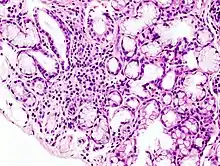

Image with a microscope of focal lymphoid infiltration in the minor salivary gland associated with Sjögren's syndrome.